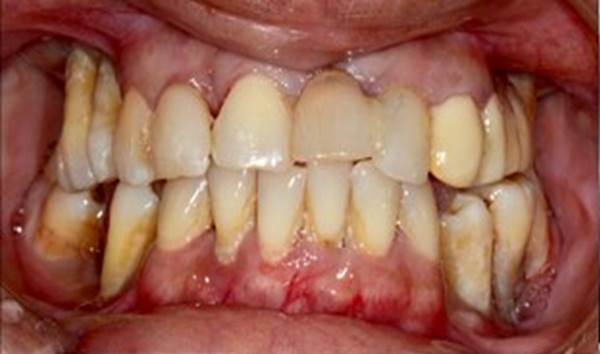

Clinical case: Full-mouth implants for mandibular & maxilla - restored using mixed prostheses

- Courtesy of Dr. Hyun Jun Kim, Korea -

“AnyRidge ensures long-term biological stability

& functionality even in

full-mouth rehabilitation case. ”